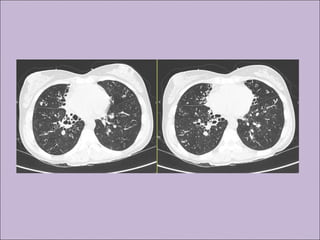

Manifestações sino-pulmonaresManifestações sino-pulmonares

C) Anormalidades persistentes à radiografia de tórax

RESPIRATÓRIAS

Bronquiectasias

Atelectasias

Manifestações sino-pulmonaresManifestações sino-pulmonares A)Colonização / infecção persistentes por patógenos típicos da FC como Staphylococcus aureus, Haemophilus influenzae, Pseudomonas aeruginosa e Burkholderia cepacia B) Tosse crônica e produtiva C) Anormalidades persistentes à radiografia de tórax D) Obstrução das vias aéreas E) Pólipos nasais, sinusite F) Baqueteamento digital Rosenstein. J Pediatr. 1998;132:389-95